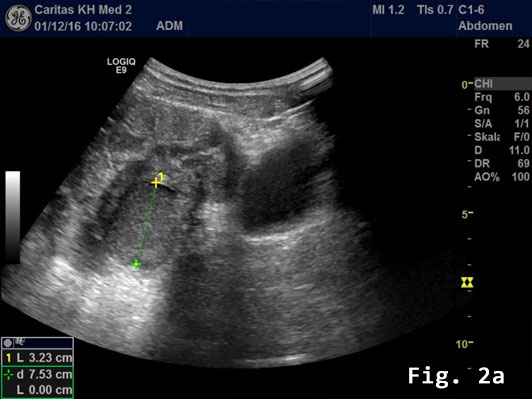

Transabdominal B-mode ultrasound (BMUS) confirmed a 40 mm sized heterogeneous hy-poechoic lesion infiltrating the sigmoid colon [Figure 2].